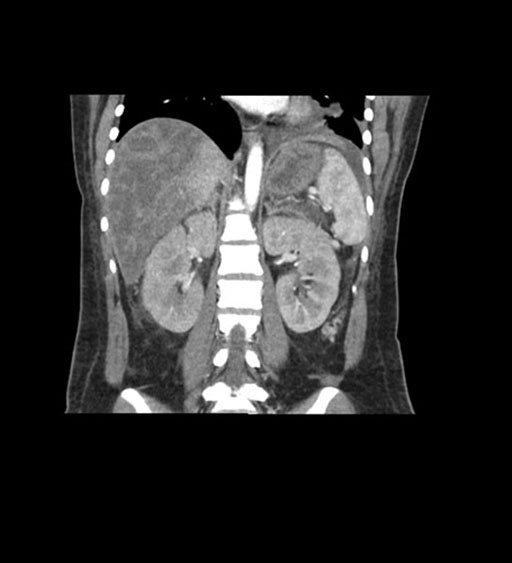

Imaging Analysis

Look through the patient's CT scan to identify any areas of concern for the necessary procedure.

Coronal Venous

Based on initial findings, which issue(s) would you be most concerned about?